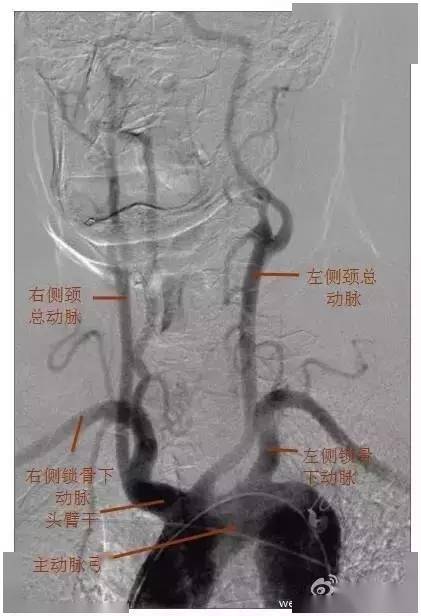

一例超高龄颅内大血管急性栓塞患者的救治

图片尺寸1500x1500